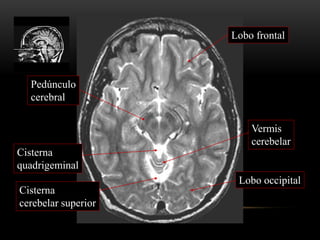

Cisterna

cerebelar superior

Pedúnculo

cerebral

Vermis

cerebelar

Lobo occipital

Lobo frontal

quadrigeminal